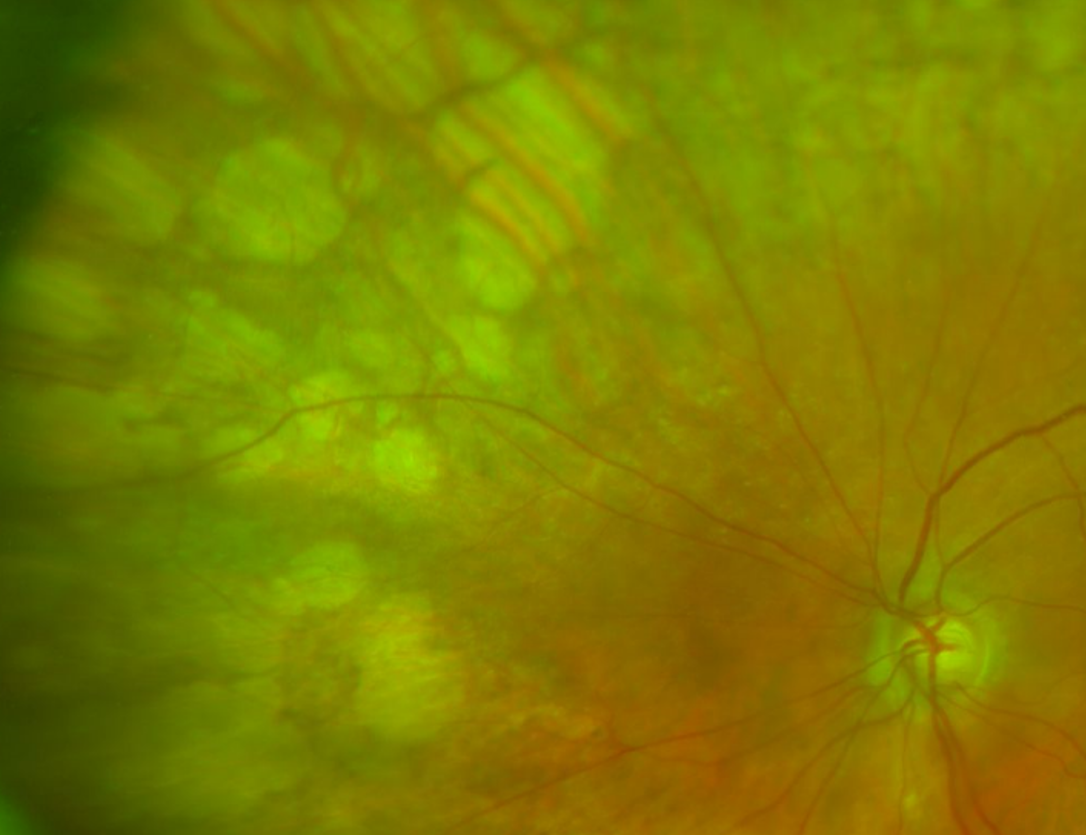

Green separation image (right eye)

More info